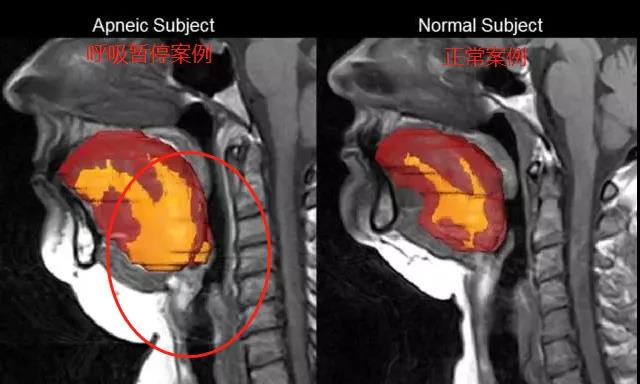

还有些人自身有点毛病,导致呼吸道比正常人狭窄:

晚上睡觉一躺下,舌根肌肉一放松,就更容易妨碍呼吸道,甚至直接堵死!

这种情况,叫“病理性打呼”。

这是一种“恶性打呼”,呼声大、不规律

有时打着突然停顿,一口气上不来!

它就是上面说的,“睡眠呼吸暂停综合征”。

得了这种病,最直接的致死因素就是:由于呼吸暂停,造成心脏缺氧,诱发心肌梗死。